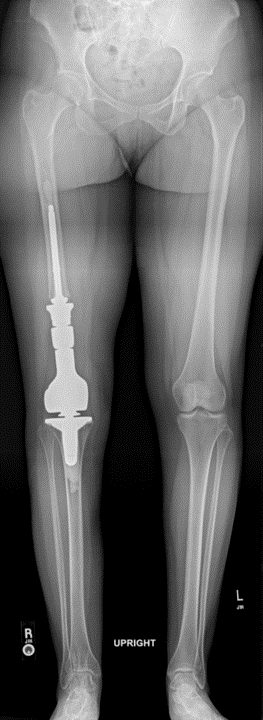

Case: 35 yo F w/ hx of osteosarcoma with painful right DFR. Progressive RLL about femoral stem. Reconstructive options? How to achieve fixation of femoral component?

Reconstructive options include revision DFR, AKA +/- osseointegrated prosthesis, or rotationplasty. After extensive discussion, rotationplasty selected in this case!